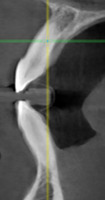

При анализе и описании компьютерной конусно-лучевой томографии (рис. 2а-г) была выявлена генерализованная первичная дегисценция вестибулярной пластинки кости от 1/2 до 3/4 длины корней зубов, зубной ряд целостный, все зубы витальны, кариозных поражений нет. Тип кости 1-2 (Lechkolm и Zarb, 1983), первичная дегисценция вестибулярной костной пластинки превышает пределы возрастной атрофии.

Через 12 месяцев (рис. 7а-г) на срезах компьютерной томограммы 11-ый и 13-ый зубы находятся в костной ткани, при этом костные пики и перегородки укрепились, объем их увеличился; вестибулярно заметен объем костной массы, предположительно компактной формации, исходя из электронной плотности участка. Этим объясняется отсутствие рецидива при лечении рецессии десны как в случае применения аутотрансплантата, также и ТМО (dura mater).